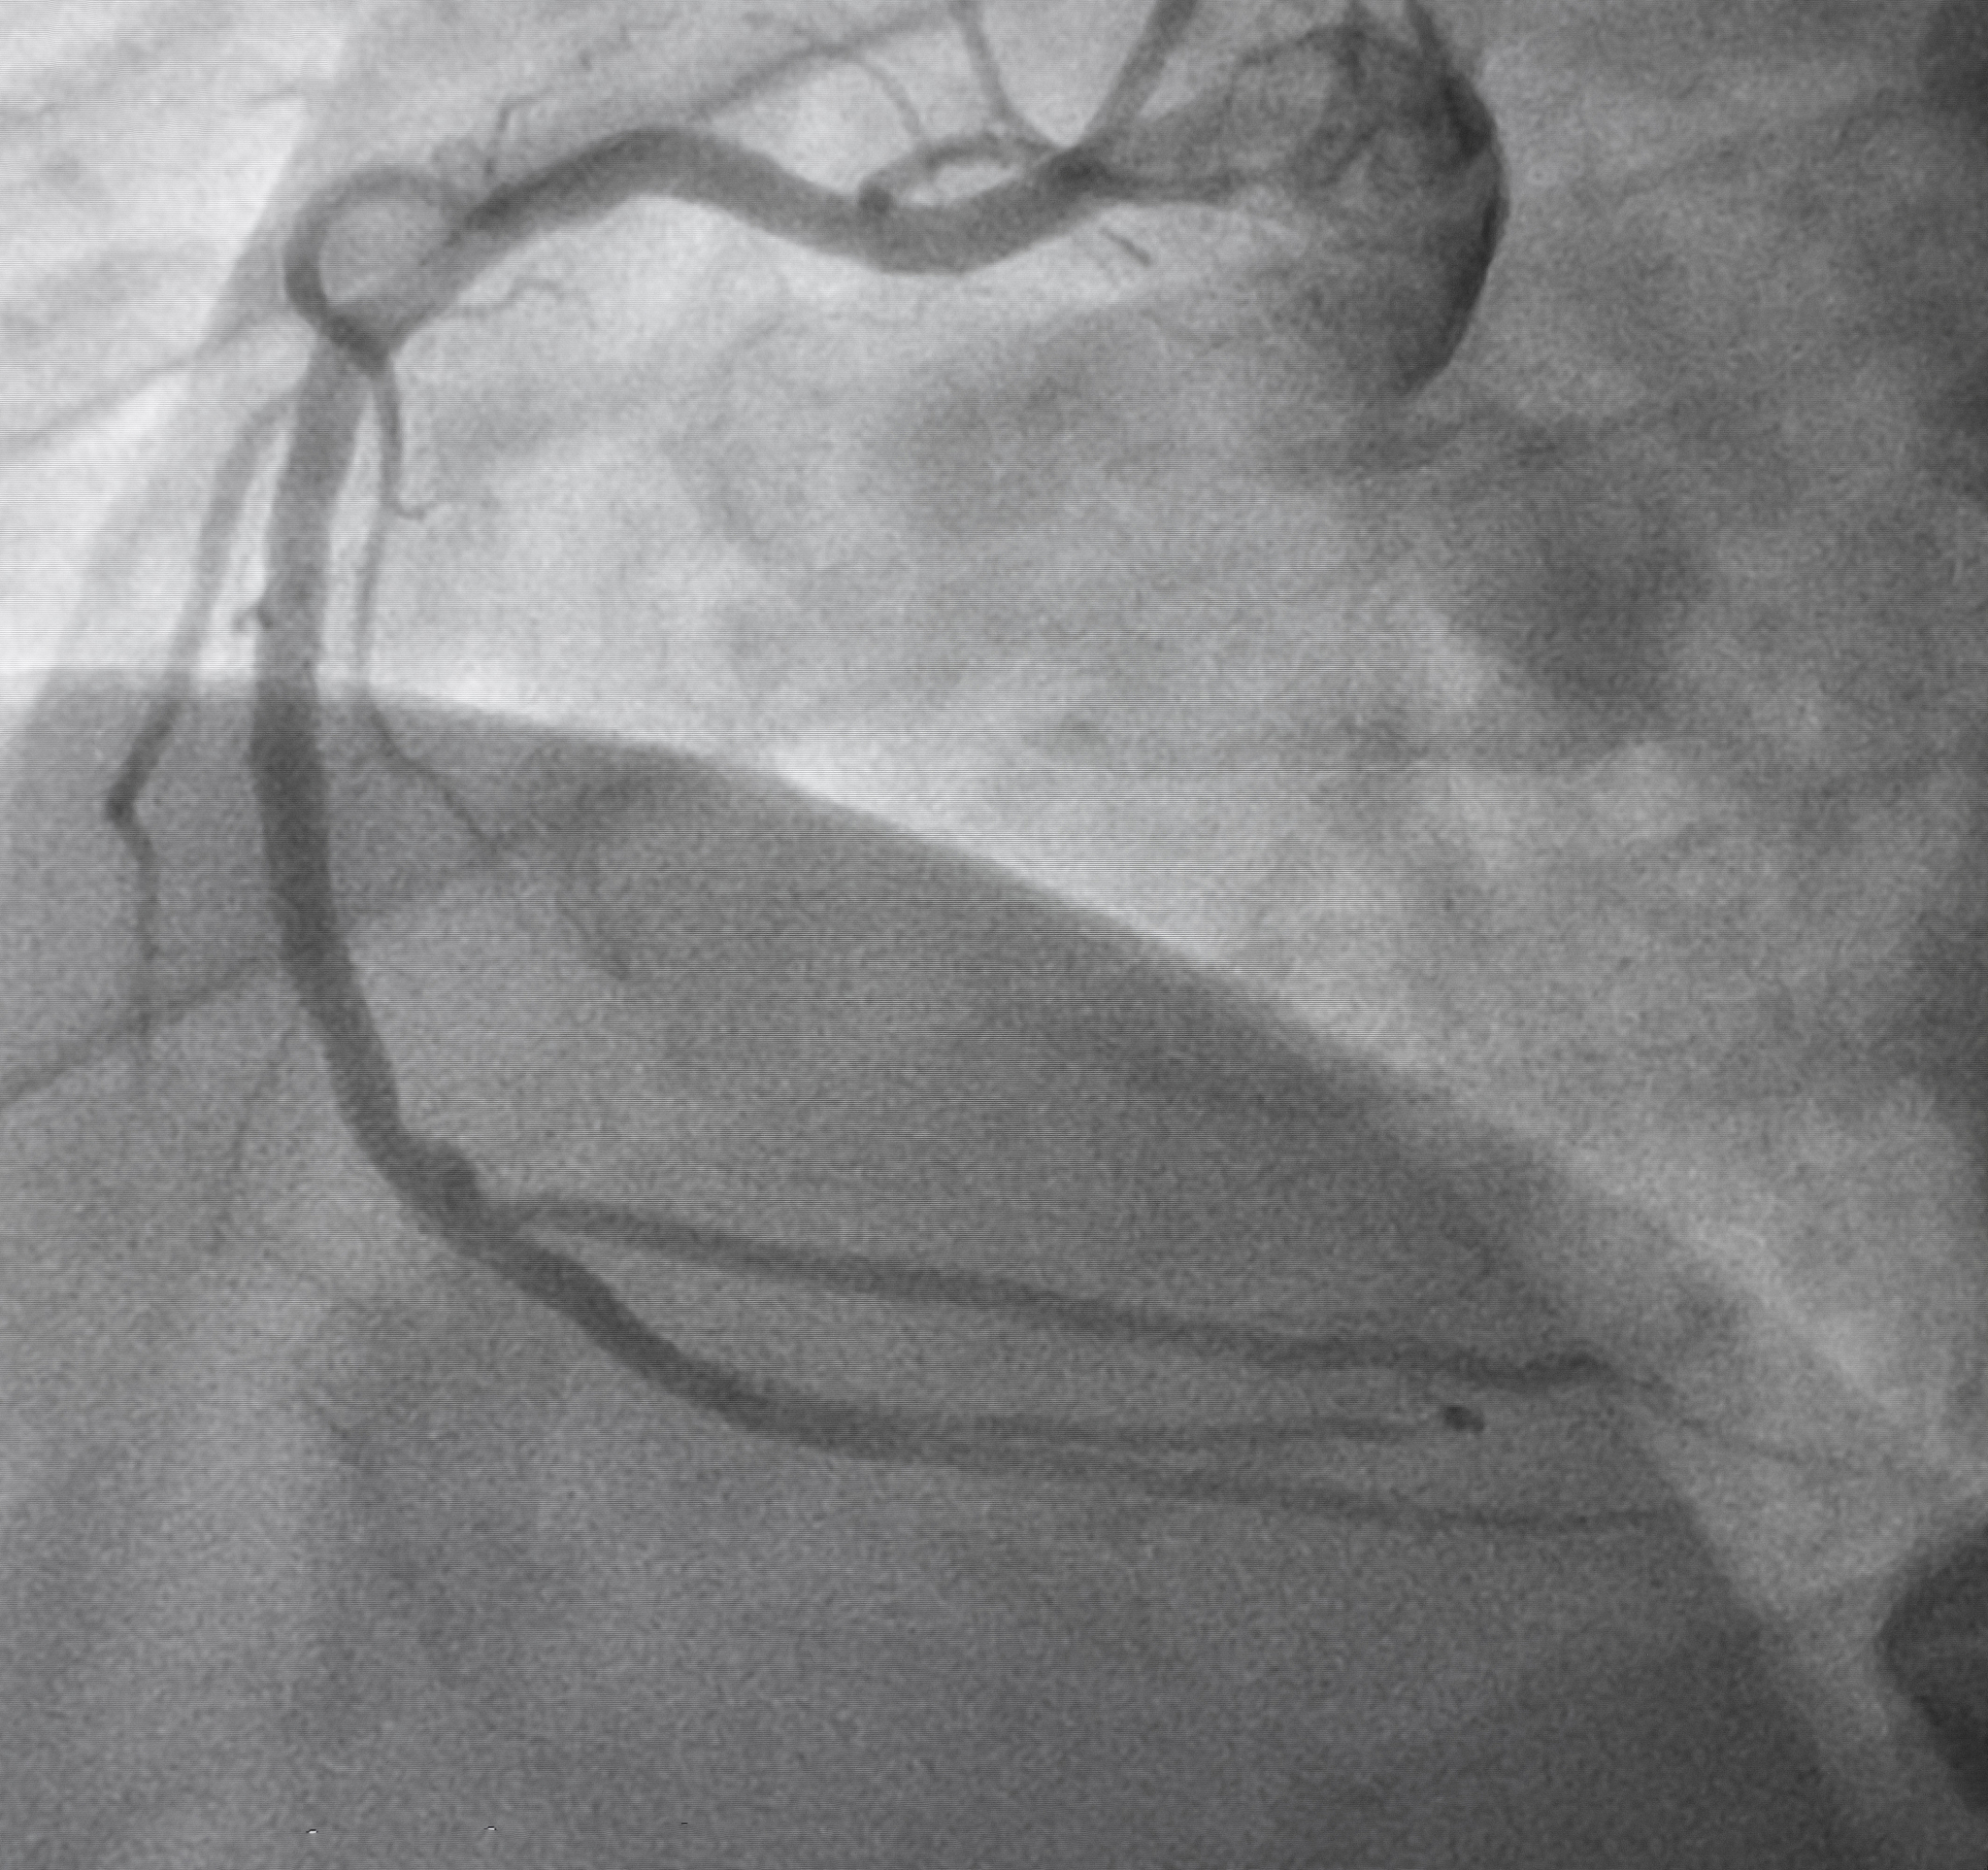

在CTA影像中,当颈动脉中的FFT至少出现在两个轴向源图像上时,就会出现'甜甜圈征'。具体表现为颈动脉腔内的充填缺损完全被造影剂包围,形成类似甜甜圈的环状影像。

'甜甜圈征'的出现是由于血液流动和CTA扫描方式相互作用造成的。当造影剂通过颈动脉时,快速的血流会导致部分造影剂被'冲走',从而在图像上形成充盈缺损。如果这种缺损出现在连续的两个或多个轴位图像上,就会形成环状的'甜甜圈'外观。